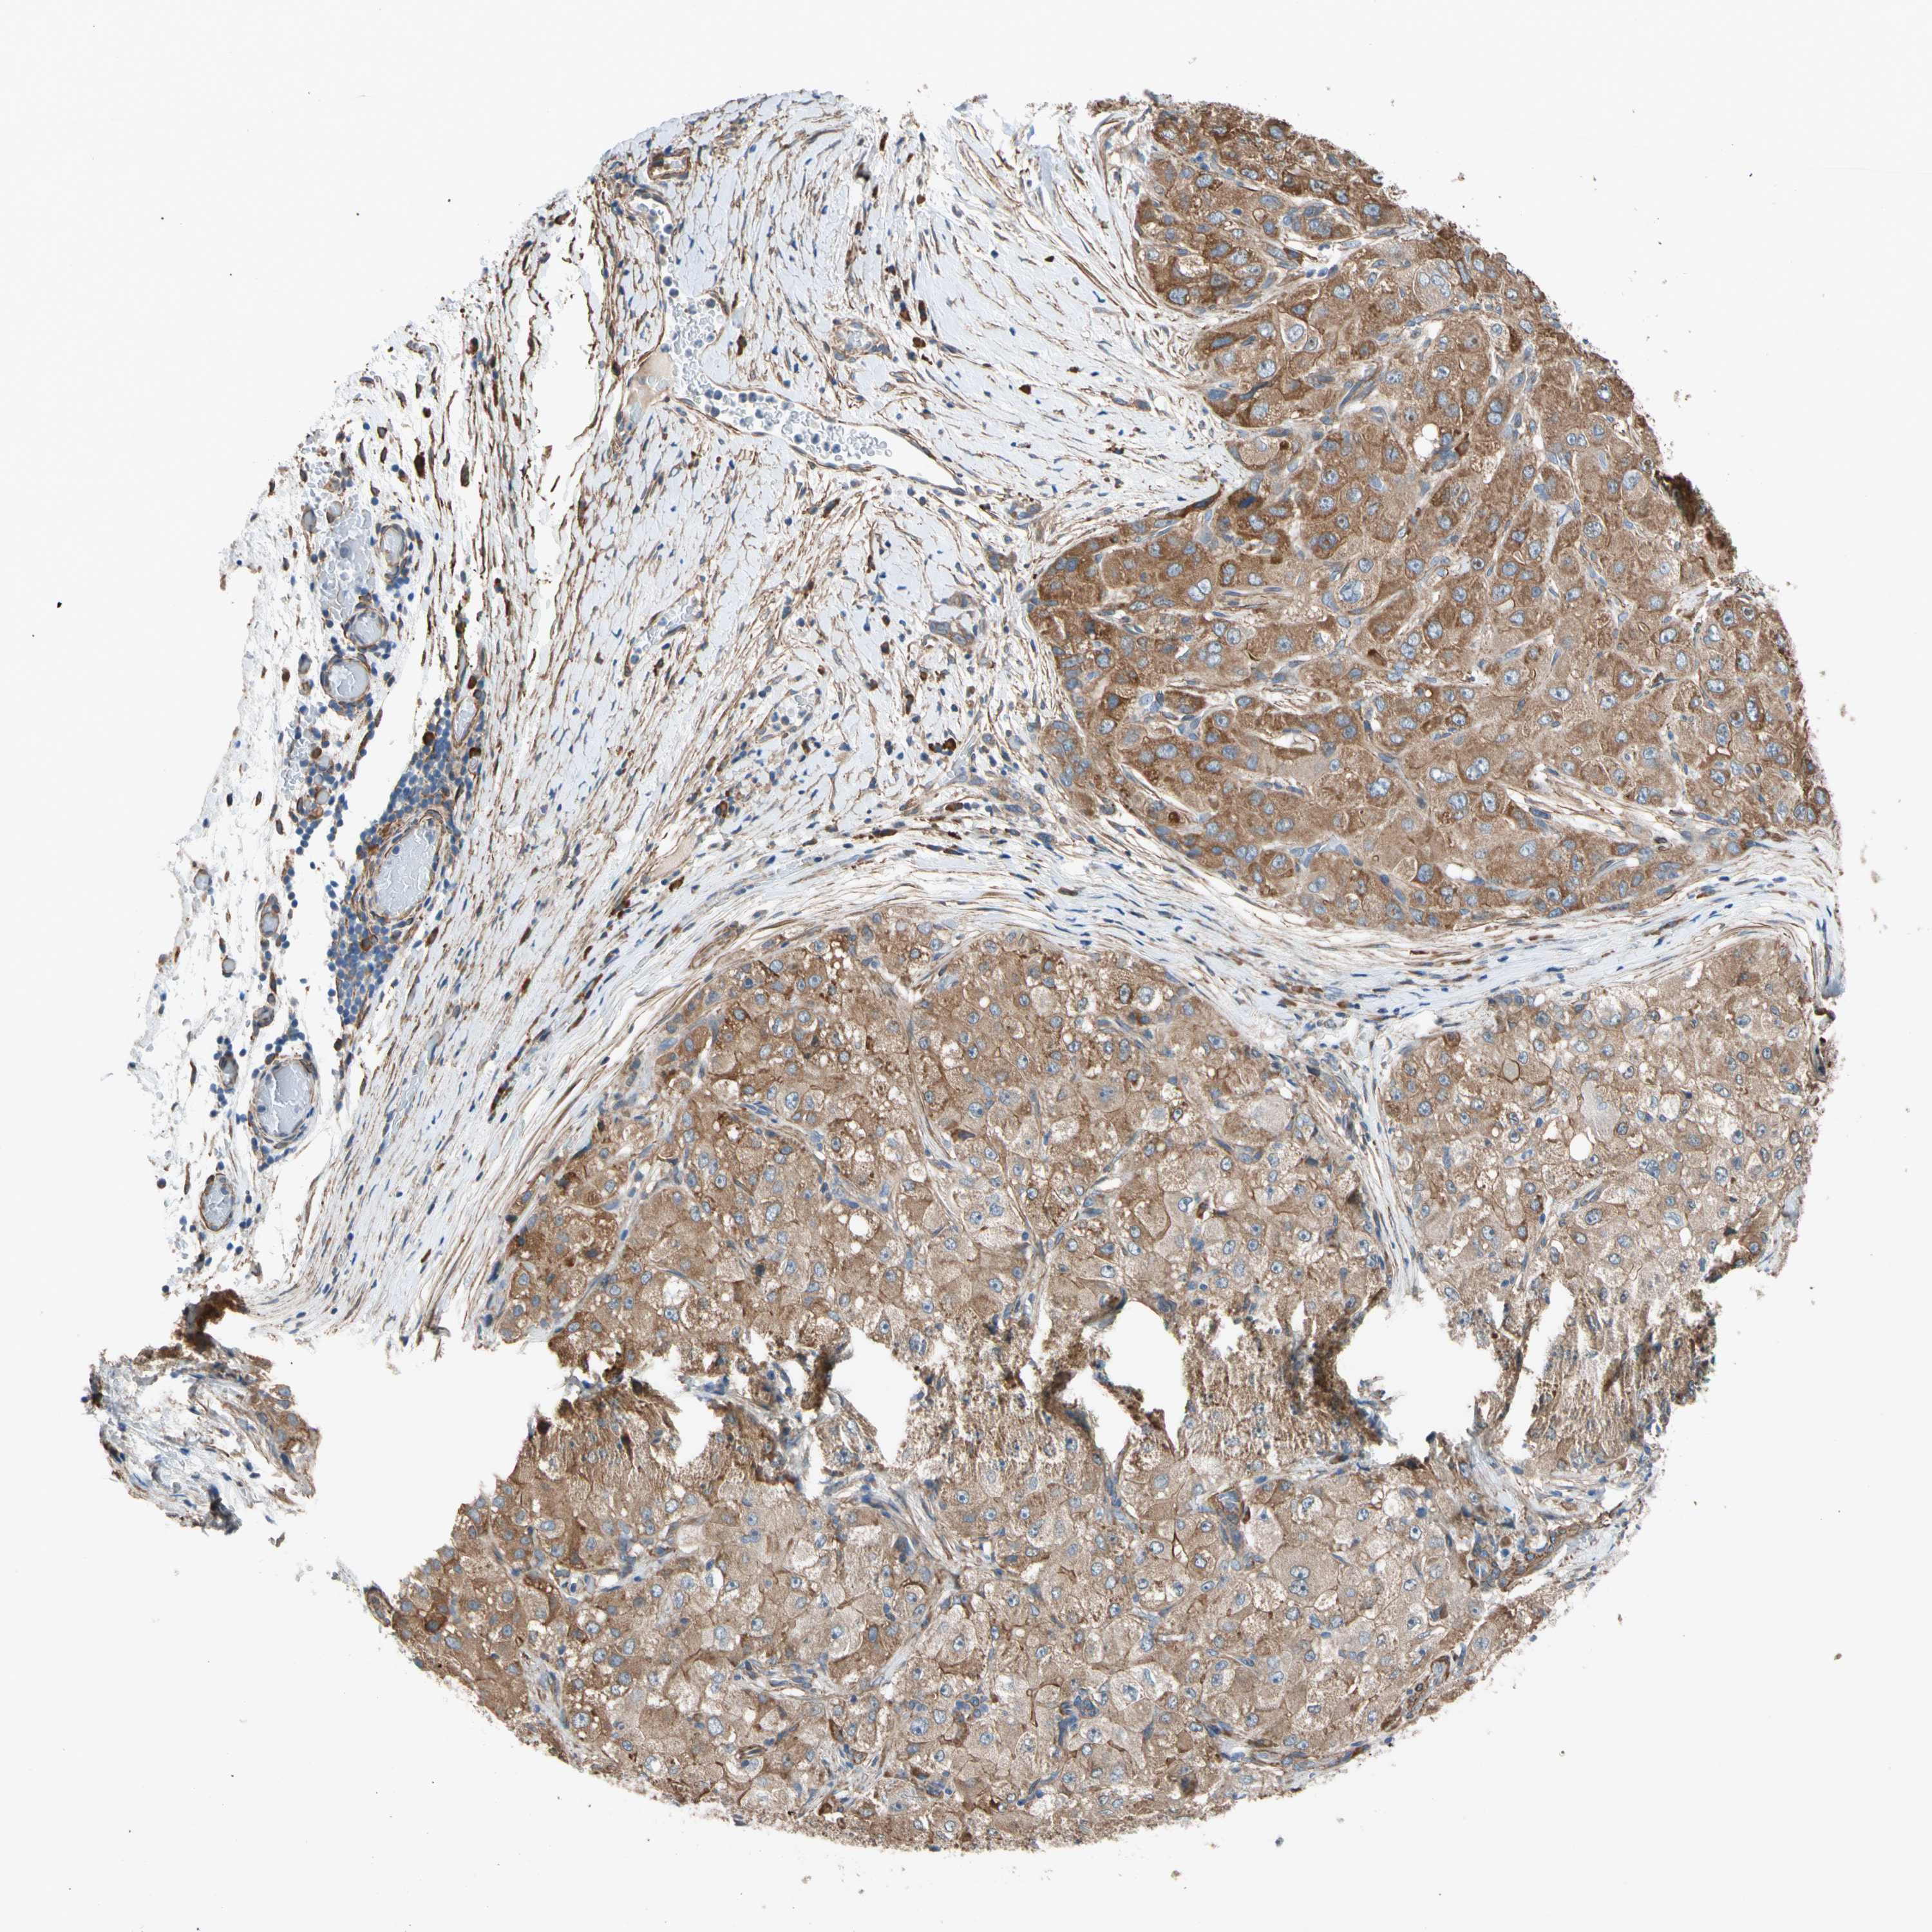

LIVER CANCER - Protein expressioni

A mouse-over function shows sample information and annotation data. Click on an image to view it in a full screen mode. Samples can be filtered based on level of antibody staining by selecting one or several of the following categories: high, medium, low and not detected. The assay and annotation is described here.

Note that samples used for immunohistochemistry by the Human Protein Atlas do not correspond to samples in the TCGA dataset.

Antibody stainingi

Antibody staining in the annotated cell types in the current human tissue is reported as not detected, low, medium, or high, based on conventional immunohistochemistry profiling in selected tissues. This score is based on the combination of the staining intensity and fraction of stained cells.

Each image is clickable and will lead to virtual microscopy that enables deeper exploration of all samples and also displays staining intensity scores, fraction scores and subcellular localization as well as patient and tissue information for each sample.

Antibody HPA008183

Antibody HPA053882

Antibody CAB019313

Staining

High

Medium

Low

Not detected

Intensity

Strong

Moderate

Weak

Negative

Quantity

>75%

75%-25%

<25%

None

Location

Nuclear

Cytoplasmic/membranous

Cytoplasmic/membranous,nuclear

Cholangiocarcinoma

Carcinoma, Hepatocellular, NOS